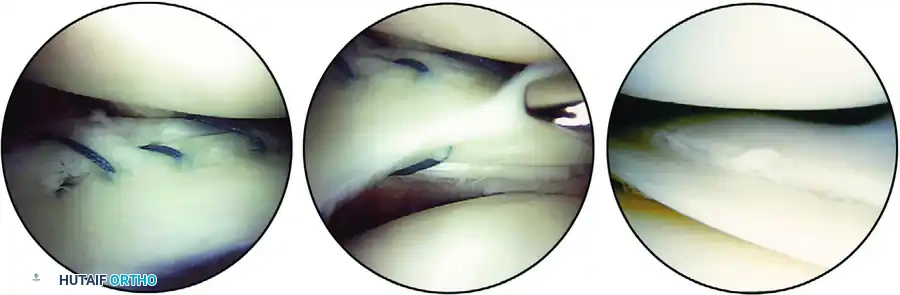

O'Connor's Classification of Meniscal Tears

While numerous classification systems exist, the O'Connor classification remains highly practical and widely utilized in orthopedic surgery. It categorizes tears into five primary patterns: (1) Longitudinal, (2) Horizontal, (3) Oblique, (4) Radial, and (5) Variations (Complex/Degenerative).

1. Longitudinal Tears and Bucket-Handle Lesions

Longitudinal tears typically result from acute rotational trauma to a previously healthy, biomechanically normal meniscus.

* Morphology: The tear is vertically oriented and runs parallel to the peripheral edge of the meniscus. It may be partial or full-thickness.

* Bucket-Handle Tears: If a complete longitudinal tear propagates extensively, it produces a displaceable inner fragment. When this inner fragment flips and displaces centrally into the intercondylar notch, it is termed a "bucket-handle" tear. This often presents clinically as a locked knee.

2. Horizontal Tears

Horizontal tears are characterized by a cleavage plane that divides the meniscus into superior and inferior leaves.

* Pathogenesis: These are predominantly degenerative in nature, occurring more frequently in older patients due to chronic shear forces.

* Location: They are most commonly observed in the posterior horn of the medial meniscus or the mid-body of the lateral meniscus. Many complex flap tears originate from an underlying horizontal cleavage component.

3. Oblique Tears

Oblique tears are full-thickness disruptions that run diagonally from the inner free edge of the meniscus outward into the meniscal body.

* Nomenclature: They are classified based on the location of their base. If the base of the tear is posterior, it is a posterior oblique tear; if anterior, it is an anterior oblique tear.

4. Radial Tears

Radial tears are vertically oriented but, unlike longitudinal tears, they extend perpendicularly from the inner free edge toward the periphery.

* Biomechanics: These tears are particularly detrimental because they disrupt the circumferential collagen fibers, severely compromising the meniscus's ability to resist hoop stresses.

* Extent: They can be incomplete or complete. An incomplete radial tear that curves anteriorly or posteriorly is often referred to clinically as a "parrot beak" tear. Tears located posterior to the popliteal tendon may occasionally heal spontaneously or with local abrasion techniques.

5. Complex and Degenerative Variations

- Flap Tears: Similar to oblique tears but usually possess a horizontal cleavage element rather than being purely vertical. They are termed superior or inferior flap tears based on which surface the flap is hinged.

- Complex Tears: These contain elements of multiple tear patterns (e.g., radial, horizontal, and longitudinal). They are typically the end-result of chronic, long-standing altered joint mechanics. The initial tear pattern is often obscured by subsequent planes of tearing.

- Degenerative Tears: A subset of complex tears presenting with marked fraying, irregularity, and multi-planar tearing, predominantly seen in the osteoarthritic knees of older patients.